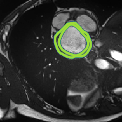

Despite their outstanding accuracy, semi-supervised segmentation methods based on deep neural networks can still yield predictions that are considered anatomically impossible by clinicians, for instance, containing holes or disconnected regions. To solve this problem, we present a Context-aware Virtual Adversarial Training (CaVAT) method for generating anatomically plausible segmentation. Unlike approaches focusing solely on accuracy, our method also considers complex topological constraints like connectivity which cannot be easily modeled in a differentiable loss function. We use adversarial training to generate examples violating the constraints, so the network can learn to avoid making such incorrect predictions on new examples, and employ the Reinforce algorithm to handle non-differentiable segmentation constraints. The proposed method offers a generic and efficient way to add any constraint on top of any segmentation network. Experiments on two clinically-relevant datasets show our method to produce segmentations that are both accurate and anatomically-plausible in terms of region connectivity.